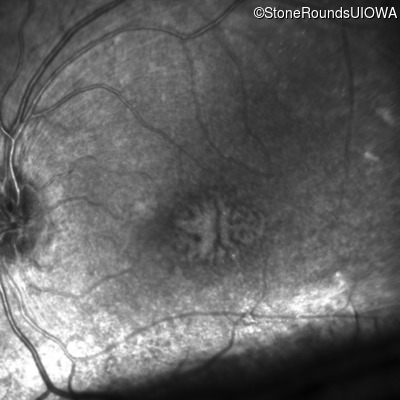

Infrared Fundus Photograph - Right - 20/500

Exemplar